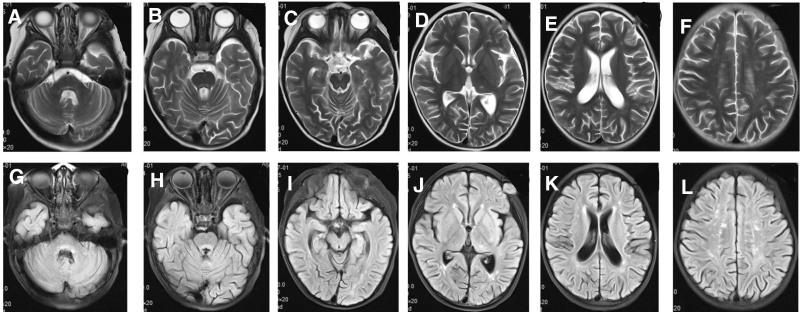

Herein, we presented 2 cases of a familial hemophagocytic syndrome caused by PRF1 gene mutation in 1 family with central nervous injury as the first symptom and searched relevant literature for clinical analysis of its pathogenic characteristics. Two children from 1 family were included in this study, both of whom had complex heterozygous mutations of C. 1189_1190dupTG (p.H398Afs*23) and C. 394G>A (p.G132R). Literature search further revealed 20 cases of PRF1 gene mutation-induced familial FHL with central nervous injury as the initial presentation. The main neurological symptoms included cranial nerve injury (81.8%), convulsion (77.3%), ataxia (63.6%), encephalopathy (59.1%), and limb paralysis (40.9%). Cranial imaging findings were dominated by the cerebral hemisphere (100%), cerebellar hemisphere (85%), brainstem (55%), and periventricular white matter (40%), and 73.7% of cases had elevated white blood cell count in CSF. Most cases were confirmed by differential diagnosis and gene sequencing, which suggested that C. 673C>T (P.r225W), C. 394G>A (P.G132r), C. 666C>A (p.H222Q), C. 1349C>T (p.T450M), C. 1349C>T (p.T450M), and C. 443C>C (p.A148G) could be focal mutations of this disease.

本研究报道了 1 家系中 2 例以中枢神经损伤为首发表现的家族性噬血细胞综合征,患儿均存在 PRF1 基因复合杂合突变,C.1189_1190dupTG(p.H398Afs*23)和 C.394G>A(p.G132R),并进行了临床分析。检索相关文献,共纳入 20 例以中枢神经损伤为首发表现的 PRF1 基因突变致家族性 FHL 患儿,主要神经系统症状包括颅神经损伤(81.8%)、抽搐(77.3%)、共济失调(63.6%)、脑病(59.1%)和肢体瘫痪(40.9%)。头颅影像学以大脑半球(100%)、小脑半球(85%)、脑干(55%)和脑室周围白质(40%)受累为主,73.7%的患儿脑脊液白细胞计数升高。大多数病例经鉴别诊断和基因测序明确诊断,C.673C>T(p.r225W)、C.394G>A(p.G132R)、C.666C>A(p.H222Q)、C.1349C>T(p.T450M)、C.1349C>T(p.T450M)和 C.443C>C(p.A148G)可能为该疾病的局灶性突变。